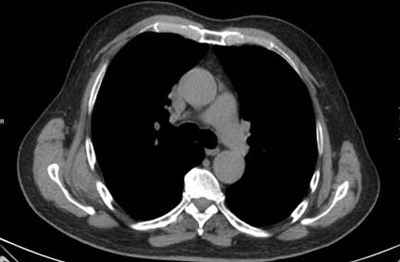

Figura 1: Imagen de TC dónde se aprecia masa 65 x 20 mm, en región subescapular.